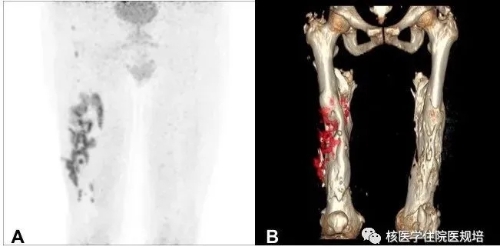

1 A:双大腿PET MIP图;BAW VR 3D重建图

右大腿软组织感染,双侧股骨骨折术后愈合不良

右股骨下段髓腔内多发FDG代谢增高灶

右股骨骨干增粗变形,骨质密度弥漫增高,中段骨皮质不连续;右股骨上段及下段骨髓腔内可见多发FDG摄取增高灶(SUVmax分布在5.05.8),CT示髓腔内密度增高;右大腿中下段软组织内见弥漫性FDG摄取增高(SUVmax11.9),累及长度约23cm,病灶外下方见窦道形成,并与骨组织相通,深约3.8cm,另软组织内见多发不规则钙化及骨化

左股骨中段骨皮质不连续,髓腔内密度弥漫增高,左大腿软组织内见分层状不规则钙化及骨化密度影,FDG摄取未见明显异常。